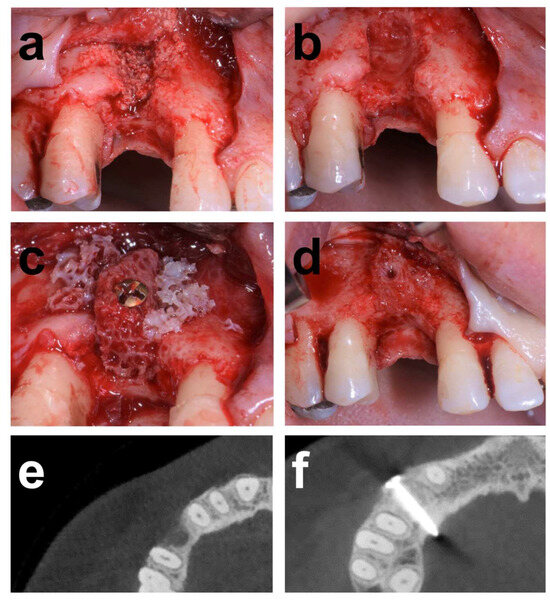

2.7.2. Case 2